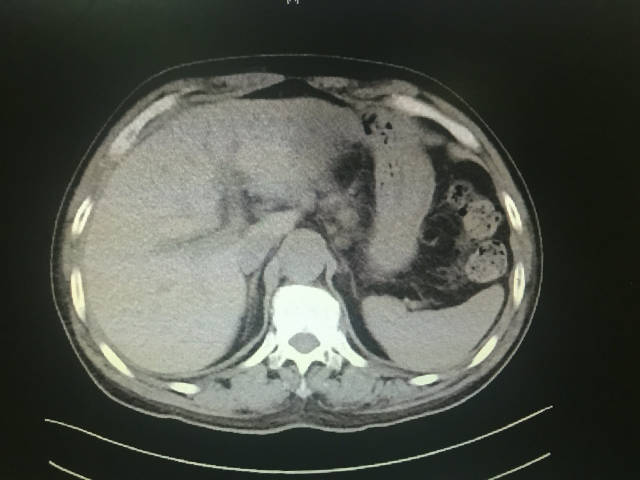

ct检查可见胆总管扩张,胆总管结石,胆囊结石,胆囊壁增厚水肿.